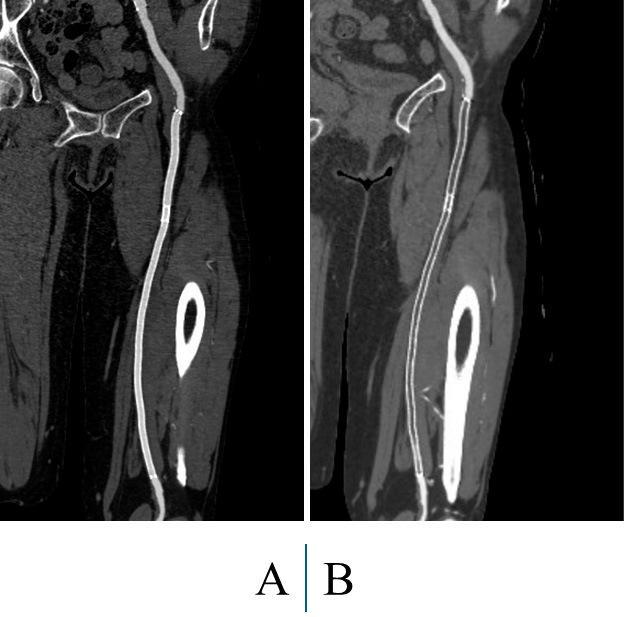

Endovascular treatment for patients with lower extremity artery disease is conducted worldwide due to its efficacy. Many studies have shown durability for patients with intermittent claudication, and various guidelines have shifted to the use of endovascular treatment. However, clinical outcomes in patients with chronic limb-threatening ischemia who undergo endovascular treatment have not been fully investigated. Generally, chronic limb-threatening ischemia cases have complex lesions such as small vessels, severe calcification, poor runoff vessels, chronic total occlusion, and long lesions, which result in poor outcomes. Thus, endovascular treatment for chronic limb-threatening ischemia cases remains challenging, despite the many technical and device advances. In 2019, the Global Vascular Guidelines were proposed for the treatment of patients with chronic limb-threatening ischemia. Here, we review previous guidelines and reports of patients with lower extremity artery disease who underwent endovascular treatment.

由于其有效性,下肢动脉疾病患者的血管内治疗在全球范围内开展。许多研究表明,间歇性跛行患者接受该治疗后效果持久,各种指南也已转向采用血管内治疗。然而,接受血管内治疗的慢性肢体威胁性缺血患者的临床结局尚未得到充分研究。一般来说,慢性肢体威胁性缺血病例存在复杂病变,如小血管、严重钙化、流出道血管不佳、慢性完全闭塞和长病变,这些都会导致预后不良。因此,尽管有许多技术和设备进展,慢性肢体威胁性缺血病例的血管内治疗仍然具有挑战性。2019年,针对慢性肢体威胁性缺血患者的治疗提出了《全球血管指南》。在此,我们回顾先前关于接受血管内治疗的下肢动脉疾病患者的指南和报告。